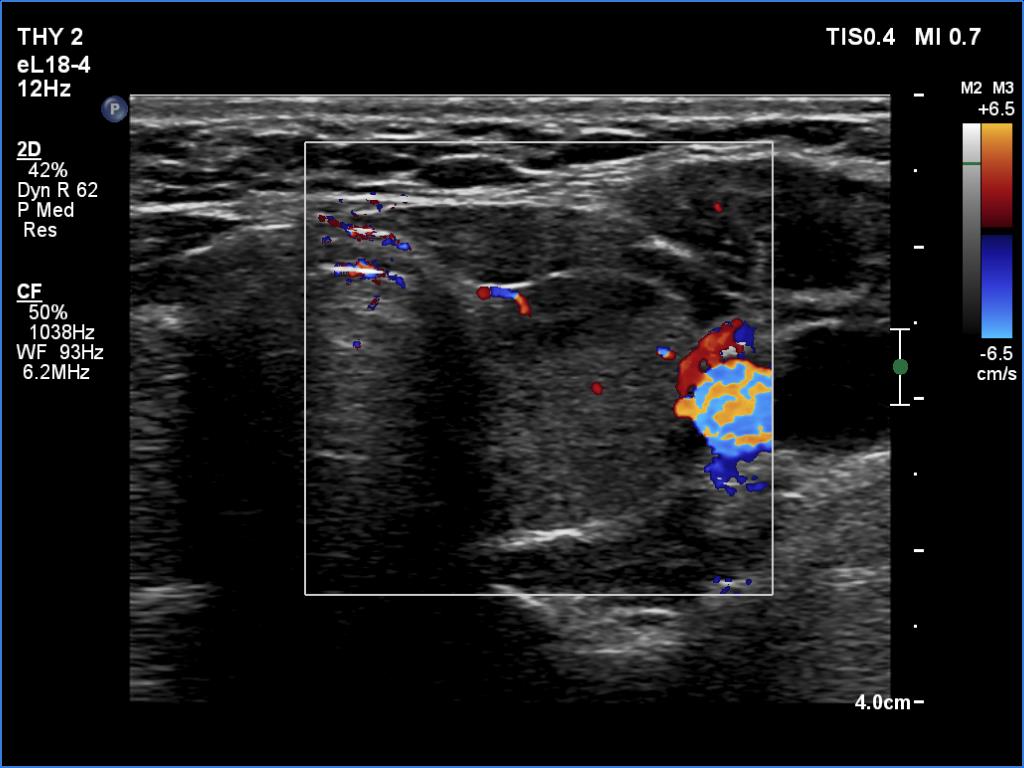

Graves' disease - case 158 (ultrasonographic picture 7)

Left lobe, transverse scan, color Doppler mode. The vascularization is decreased.